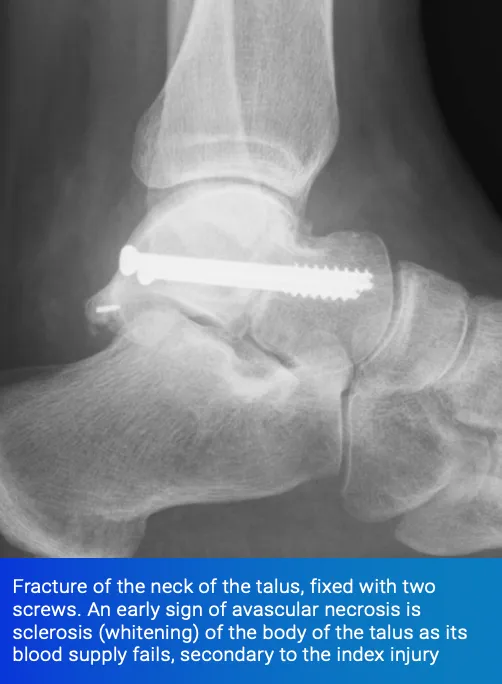

4) Damage to the Blood Supply - Avascular Necrosis

Certain fractures are renowned for damaging the blood supply of the bone. Common examples are fractures of the hip and fractures of the talus, the main bone in the ankle joint.

Talar neck fractures, if caused by a high-energy injury with significant displacement, can completely disrupt the blood supply to the body of the talus. This can cause the bone to die and collapse, resulting in arthritis and may necessitate salvage procedures such as fusions around the hindfoot.